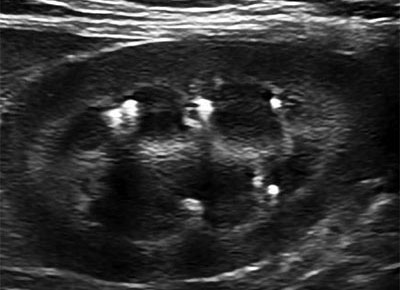

⑤ 多発性のう胞腎

下記項目参照

① 多発性のう胞腎

猫(スコティシュホールド)

スコティシュは、遺伝的な背景が高いと考えられる

猫(雑種)

発生初期は、血液検査ではわからないことが多い。やせ型の猫は、超音波検査が重要となる。

PKDは、初期~中期では、血液検査に引っかからないことが多い。特に純系の猫で、やせ型、体重が増えないような場合は、避妊手術などの際には、必ず腹部の画像診断をすべきです。PKDは、脾臓にも、嚢胞を伴うことがあります。